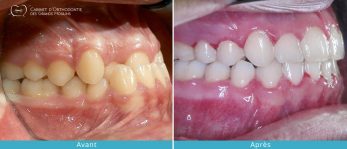

- Améliorer l’esthétique du visage et du sourire ce qui peut améliorer la qualité de vie personnelle et professionnelle.

- Rétablir une mastication efficace.

- Réduire les dysfonctions articulaires (craquements, douleurs, blocage, ) en améliorant l’occlusion dentaire et en corrigeant les décalages dentaires et squelettiques.